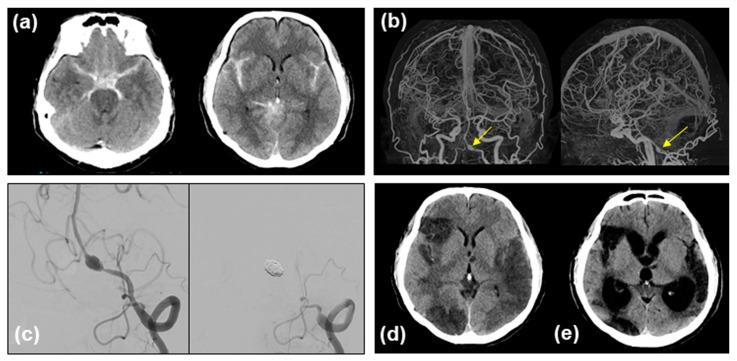

Clazosentan prevents vasospasms after aneurysmal subarachnoid hemorrhage (SAH). However, clinical data on patients with SAH with ruptured vertebral artery dissecting aneurysms (VADAs) are limited. We report the case of a 49-year-old male patient with mild-grade (WFNS grade 1) thick and diffuse (modified Fisher grade 3) SAH who underwent endovascular trapping of a ruptured VADA, resulting in a poor functional outcome with a modified Rankin Scale score of 4 due to severe symptomatic vasospasm refractory to clazosentan, requiring repeated rescue endovascular therapies and chronic communicating hydrocephalus. A retrospective analysis of the clot density in the basal and Sylvian cisterns, assessed by the Hounsfield unit (HU) values of serial CT scans, in this patient showed persistent higher values, distinct from another VADA case that showed a decline in HU values with a good clinical course. These results imply the limited effectiveness of clazosentan in cases of thick and diffuse SAH after a ruptured VADA, even in good-clinical-grade patients treated with less invasive modalities. The HU values may become a simple quantitative marker for predicting symptomatic vasospasms and chronic hydrocephalus.

克拉生坦可预防蛛网膜下腔出血(SAH)后的血管痉挛。然而,关于破裂椎动脉夹层动脉瘤(VADA)的 SAH 患者的临床数据有限。我们报告了一例 49 岁男性患者,其为轻度(WFNS 分级 1)厚且弥漫(改良 Fisher 分级 3)SAH,接受了破裂 VADA 的血管内夹闭术,由于严重的症状性血管痉挛对克拉生坦无反应,需要反复进行血管内救援治疗和慢性交通性脑积水,导致功能预后不良,改良 Rankin 量表评分为 4。对该患者的基底池和外侧裂池的血栓密度进行回顾性分析,通过连续 CT 扫描的亨氏单位(HU)值评估,发现持续存在较高的 HU 值,与另一例 HU 值下降、临床过程良好的 VADA 病例不同。这些结果表明,即使在接受侵袭性较小的治疗方式的良好临床分级患者中,克拉生坦在破裂 VADA 后发生厚且弥漫性 SAH 时的疗效有限。HU 值可能成为预测症状性血管痉挛和慢性脑积水的简单定量标志物。